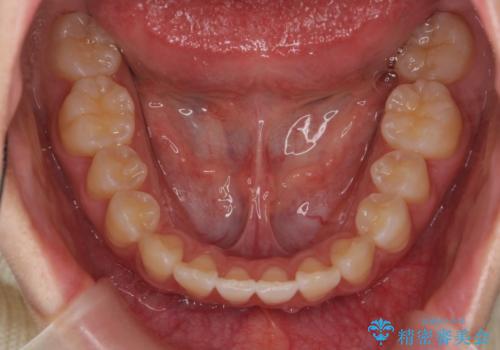

出っ歯 軽度のがたつき インビザラインで

- 20代女性

- インビザライン

- 奥歯を後ろに下げる処置をおこなっています。

前歯にオープンバイト気味の症状がありましたが、前歯を後ろに下げることでしっかりかませています。

前歯のずれも治り、しっかり下がりました。

前歯を下げるのに、顎間ゴムを使用していただいています。